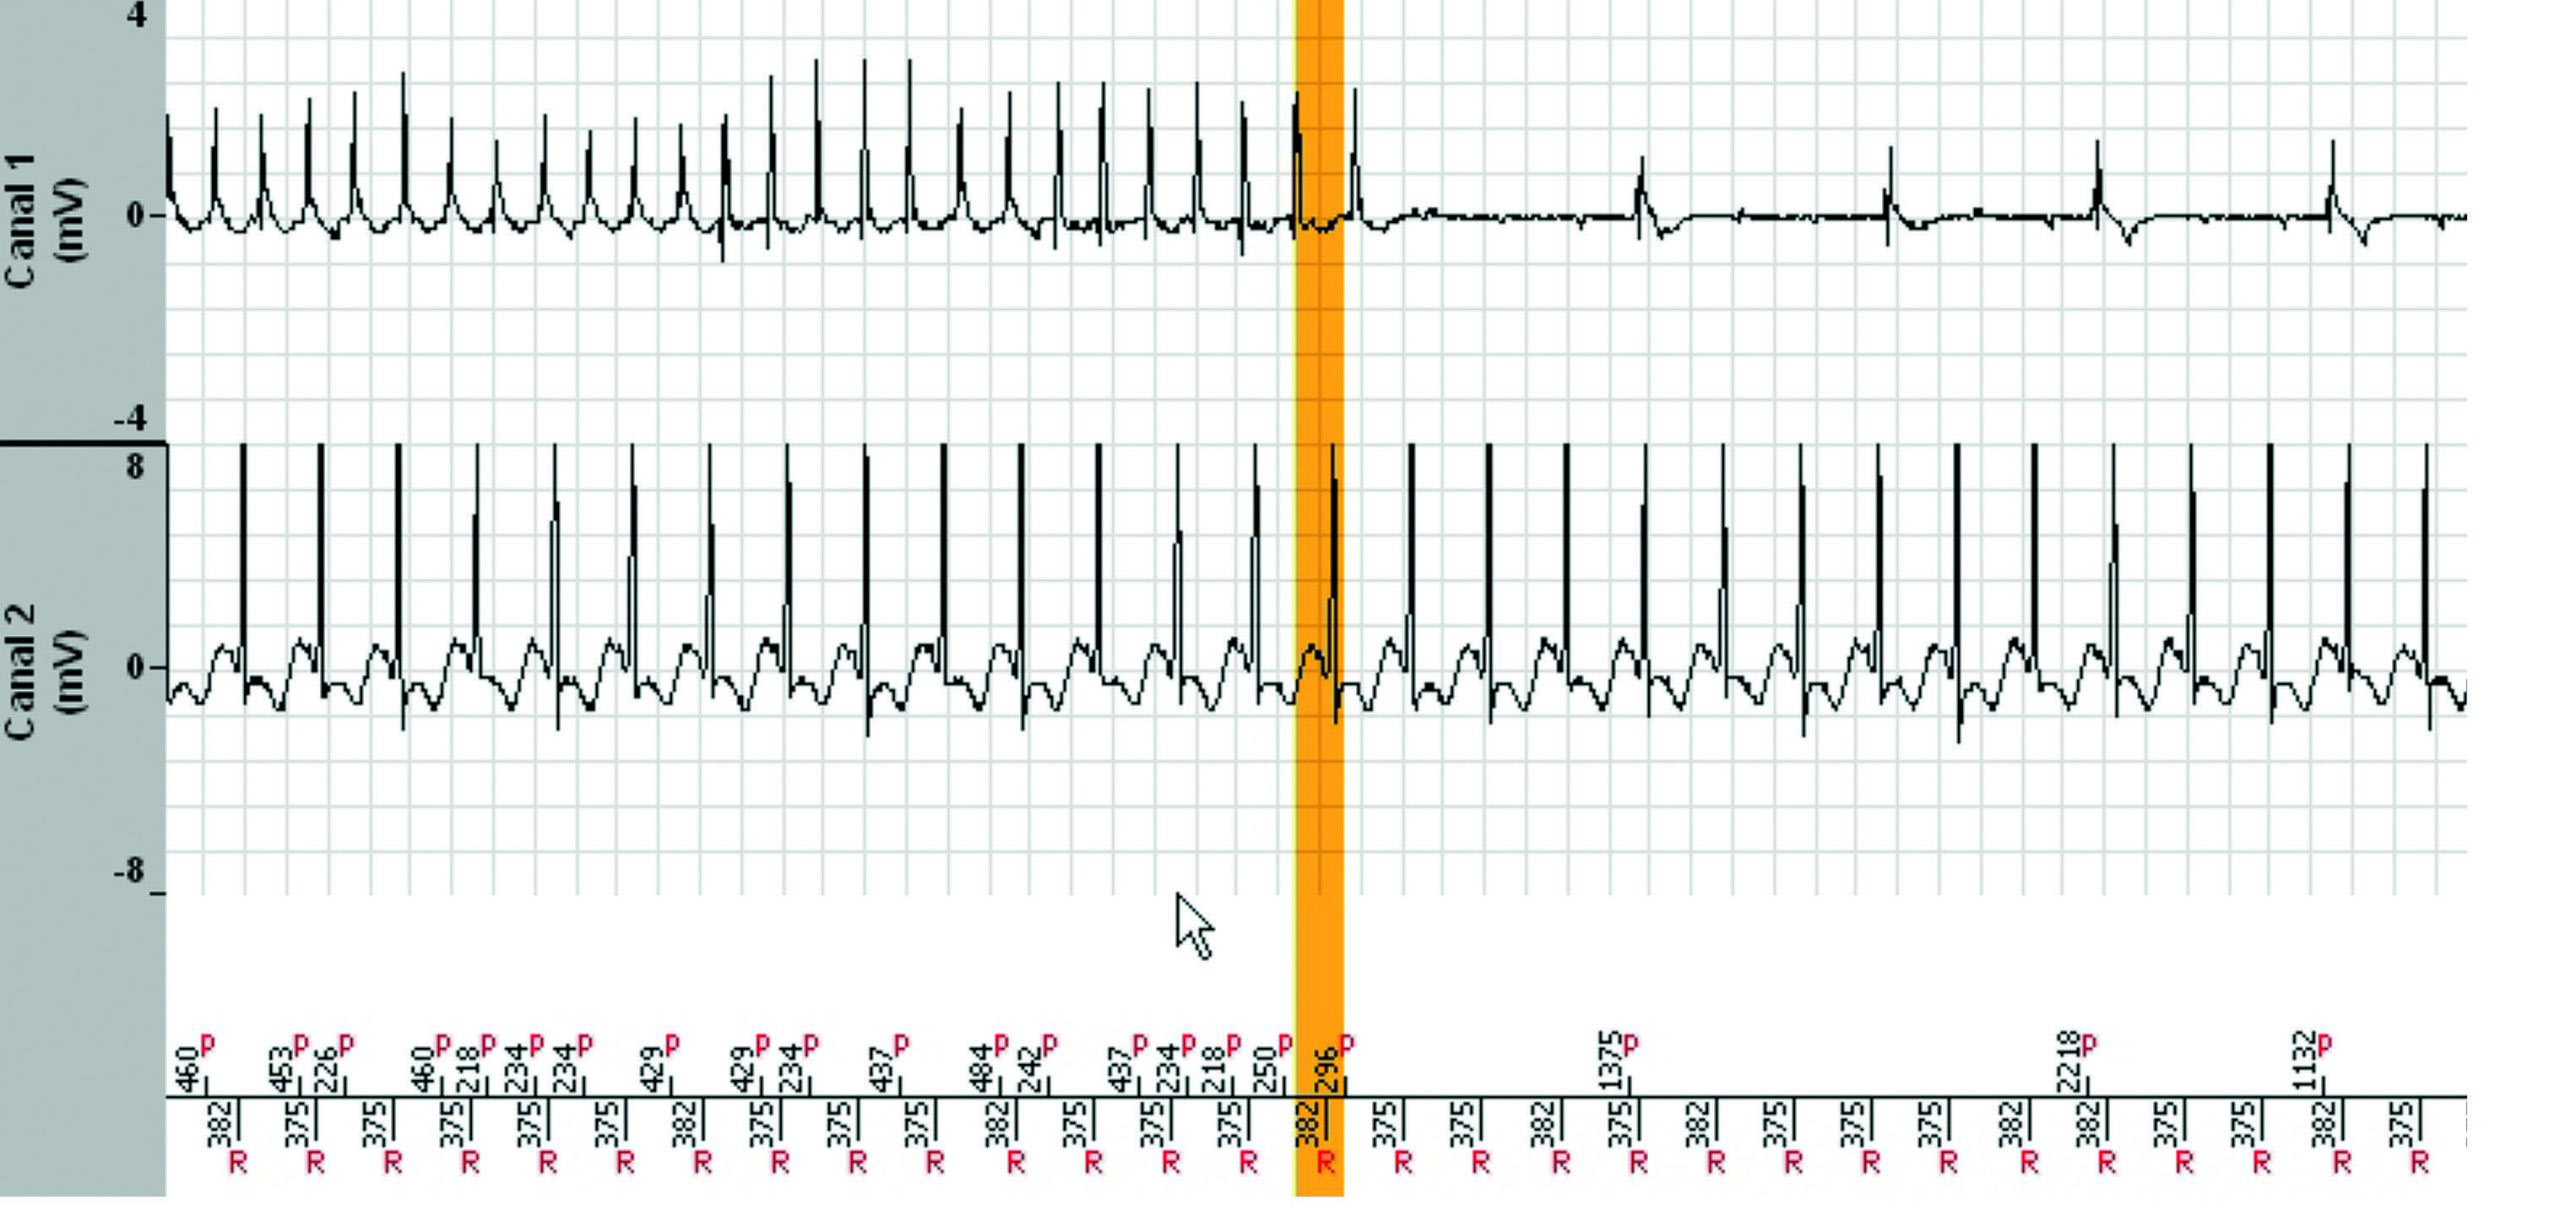

L'épisode a duré 7 minutes et 38 secondes et le tachogramme ci-dessous ne montre que les 3dernières minutes. Pendant les 4 minutes et 30 secondes précédentes, la fréquence ventriculaireest parfaitement stable dans la zone de TV lente.